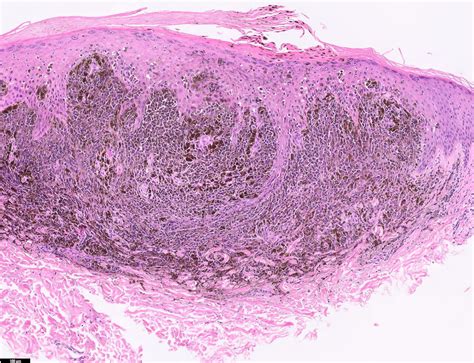

Malignant Melanoma Nodular

Malignant melanoma nodular represents a subtype of invasive melanoma characterized by its distinct, dome-shaped appearance. While many melanomas develop from existing moles or appear as flat, spreading lesions, the malignant melanoma nodular variety typically presents as a firm, raised bump that stands out from the surrounding skin. Because it grows vertically into the dermis rather than horizontally, it is often more advanced at the time of diagnosis compared to superficial spreading melanoma.

This type of cancer develops in the melanocytes, the cells responsible for producing melanin, which gives skin its color. In the case of nodular melanoma, these cells undergo mutations that cause them to grow uncontrollably and push downward into deeper tissue layers. This vertical growth phase is exactly why it is considered so dangerous, as it allows the cancer to reach blood vessels and lymph nodes more quickly, increasing the risk of metastasis.

When a physician suspects malignant melanoma nodular, they will perform a physical examination followed by a biopsy. A biopsy is the only definitive way to diagnose skin cancer. During this procedure, the entire lesion or a representative portion is removed and sent to a pathologist for microscopic analysis.